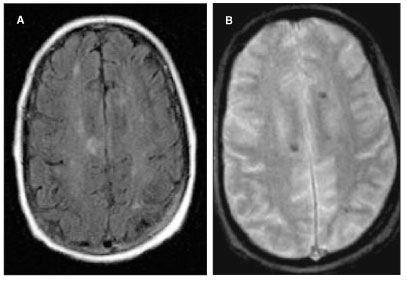

On the third hospital day, gadolinium MRI of the brain performed to evaluate anisocoria revealed a dominant 1.1 x 1.7-cm lesion with surrounding edema. Heme-sensitive sequencing demonstrated susceptibility artifacts around the lesion in the right temporal lobe consistent with associated hemorrhage (Figure 1). Subtle enhancement was also present, although no intense enhancement for pre-T1 hyperintense characteristics was seen (Figure 2, A and B). This dominant lesion was hyperintense on T2-weighted images consistent with surrounding edema and central hypointensity (Figure 2, C). This lesion also showed a smaller internal area of T2 hyperintensity that was not hyperintense on T1-weighted images. In addition, multiple tiny hemorrhagic lesions without marked edema were scattered throughout the cerebral white matter, notably in the corticomedullary junctions (Figure 3, A and B).

Figure 3.Axial fluid-attenuated inversion recovery (FLAIR) brain MRI scan demonstrating peripheral tiny lesions without marked edema (A). Axial gradient brain MRI scan with associated hemorrhage around the peripheral tiny lesions (B).